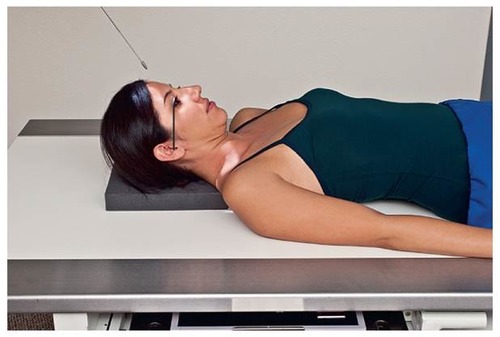

SMV for Zygomatic Arches

Part Position: Vertex on IR; IOML parallel to IR.

Central Ray: Perpendicular to IOML, entering at mid-throat, 1 inch posterior to outer canthi.

Collimation: 8×6 c/w